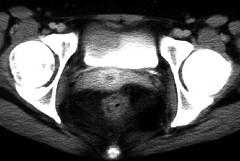

问题 女,32岁,腹痛、腹泻、便秘交替出现,粘液血便半年,里急后重,影像检查如图,最佳的诊断是 ( )

选项 A、溃疡性结肠炎 B、肠结核 C、慢性结肠炎 D、过敏性结肠炎 E、结肠癌

答案 A